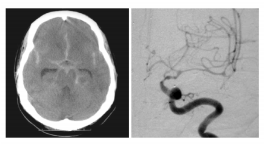

Uma mulher de 66 anos foi admitida na emergência com hemorragia subaracnoidea (HSA) aneurismática aguda e submetida a um procedimento de clipagem, permanecendo em UTI no pós-operatório. No décimo dia após o procedimento, ela começou a apresentar fala arrastada, com piora na inclinação facial para a direita e fraqueza no braço direito. Ela também estava bastante sonolenta, com muita dificuldade para despertar. Foram realizadas tomografia computadorizada de crânio sem contraste e angiografia, mostradas a seguir. Qual alternativa apresenta o melhor tratamento para o caso?